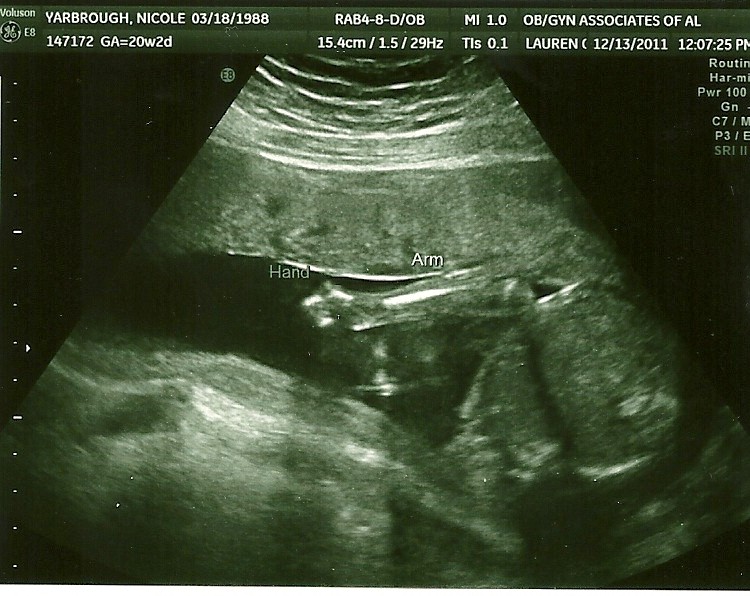

Today was our 20 week checkup, which is a big deal considering they do an ultrasound that checks all the organs closely to make sure everything is forming and working properly. We were very anxious about today. We were so worried something would be wrong with our sweet angel. We had the ultrasound first and thankfully everything was great! The technician even used the word "perfect" a few times :) Jonah's heart, brain, spine, kidneys, stomach and bladder look good and all of his measurements are right on track. He weighs 13 oz right now (6oz up from our appointment 3 weeks ago!), and his heart rate was 150. He cooperated like a good little boy for all of the important stuff, but when we tried to get a good look at his profile to see his nose and lips, he had enough! He was turned around facing my back and would not turn over no matter how much poking and jiggling we did. When the technician could angle the probe enough to see his face a little bit, he had both arms up by his face! He was being stubborn. But, I guess that's ok. He's had his picture made quite a lot. This is our 4th ultrasound!